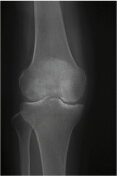

右膝

病気の進行とともに内側の関節の隙間(軟骨層)が狭くなり、やがて消失します。骨棘(こつきょく:棘のような余分な骨)も形成されてきます。そうなると正常ではまっすぐな脚が徐々にO脚に変形します。